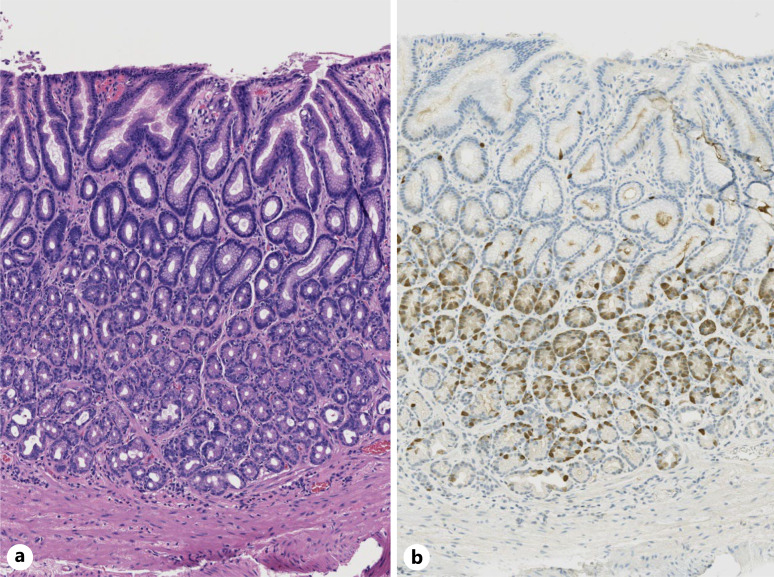

Case presentation: A 51-year-old female with a history of a Nissen fundoplication for refractory reflux presented with a 3-month history of heartburn, diarrhea, and 55-pound weight loss. Evaluation included negative upper and lower endoscopies with biopsies and negative MR enterography. A 48-h fecal fat study revealed 501 g of stool and 51 g of fat per 24 h. A serum gastrin level off PPI was elevated at 589 pg/mL with a gastric pH of 2 on gastric aspirate. An EUS, DOTATATE PET scan, and secretin stimulation test were negative for ZE. A standardized test meal with serial gastrin monitoring demonstrated an 8-fold increase in serum gastrin. Open abdominal exploration and intraoperative ultrasound showed no evidence of a gastrinoma and an antrectomy and Billroth II anastomosis was performed in treatment of G-cell hyperplasia. Pathology demonstrated a moderately increased G-cell population. Postoperatively, her hypergastrinemia and steatorrhea resolved and she regained 60 pounds.